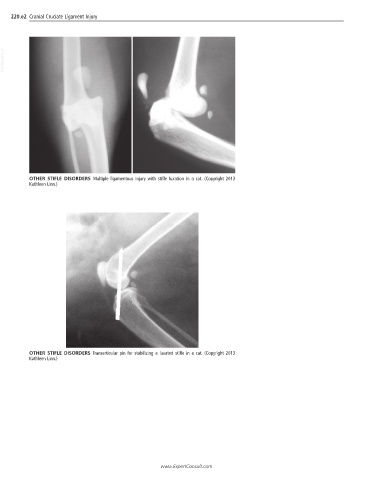

OTHER STIFLE DISORDERS Multiple ligamentous injury with stifle luxation in a cat. (Copyright 2013

Kathleen Linn.)

OTHER STIFLE DISORDERS Transarticular pin for stabilizing a luxated stifle in a cat. (Copyright 2013